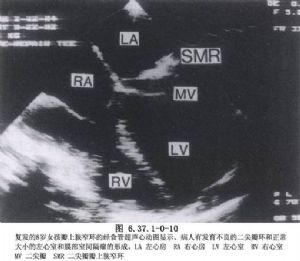

在瓣膜修复手术中,因为本病畸形的多样性,修复手术必须根据这些病理改变采用个性化手术。该手术是一种技术要求高、难度大的工艺性手术,需有经验的外科医生施行(图6.37.1-0-7~6.37.1-0-10)。